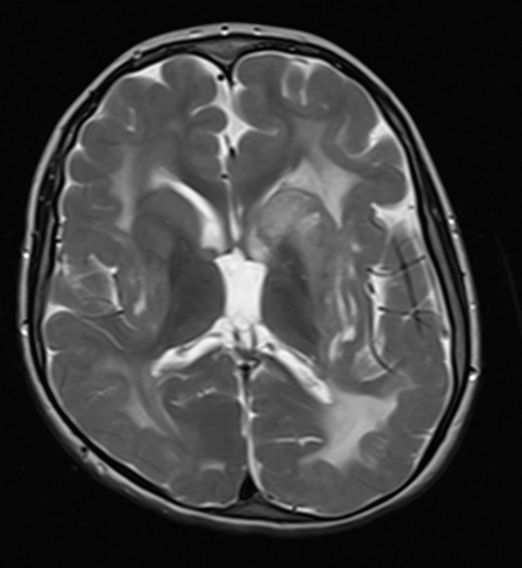

Images from the most recent brain MRI are below. The axial and coronal are T2 and the sagittal T1. Aside from the thinning of the posterior corpus callosum, no abnormality was described.